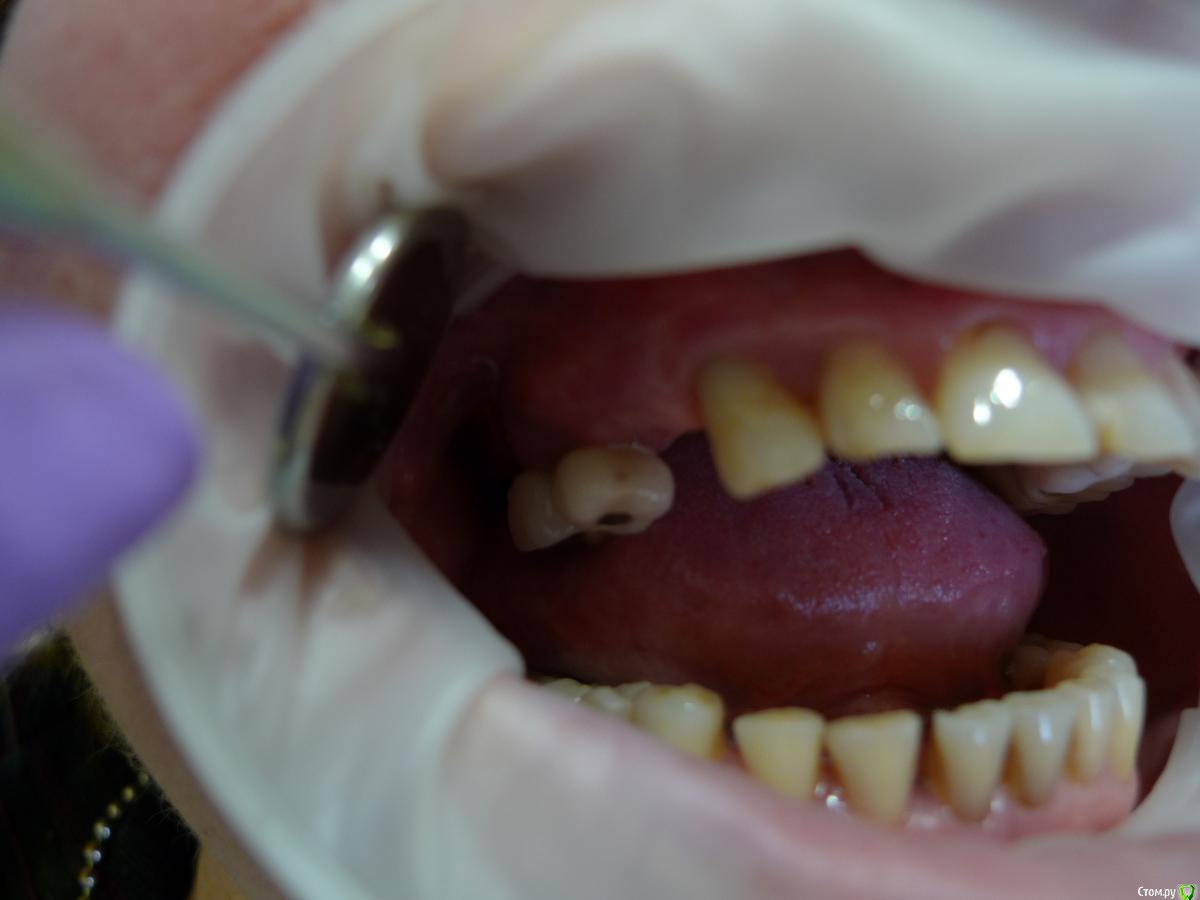

alekszander Опубликовано 26 февраля, 2016 Автор Поделиться Опубликовано 26 февраля, 2016 Прилагаю фото в полости рта (прошу прощения фото на мыльницу Leica) - ретракторов и зеркал пока нет. Ссылка на комментарий

Евгений Ходыкин Опубликовано 26 февраля, 2016 Поделиться Опубликовано 26 февраля, 2016 Ты чот видишь по фоткам этим? Ссылка на комментарий

alekszander Опубликовано 26 февраля, 2016 Автор Поделиться Опубликовано 26 февраля, 2016 Ты чот видишь по фоткам этим? согласен - фотки гумно. Но какие получились, не зеркалка же(хотя привык на нее фотать но в другой клинике) Ссылка на комментарий